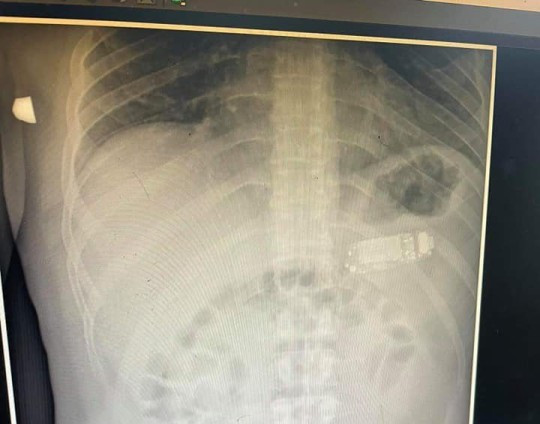

| Người đàn ông ở Kosovo nuốt chừng chiếc điện thoại di động vào bụng |

| Chiếc điện thoại có thể được nhìn thấy qua ảnh chụp X-quang. Ảnh: Metro |